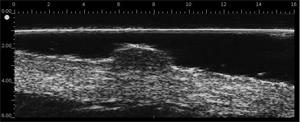

DERMCUP: ultrasonido de alta resolución para la exploración de la piel

Ultrasonido de alta resolución para la exploración de la piel

DERMCUP permite la adquisición no invasiva de secciones verticales de la piel in vivo

25 MHz: 16 mm x 12 mm

La dermis es ecogénica. Los ecos provienen de la red de fibras de colágeno y fibras elásticas. En relación a la dermis, las lesiones (tumores, quistes, angiomas …) aparecen como áreas hipoecoicas.

Gracias a su frecuencia de 25 MHz y 50 MHz , el DERMCUP ofrece una alta resolución:

Axial: 30 μm

Lateral: 120 μm

En dermatología, es necesario visualizar lesiones infra-centimétricas. Esto no se puede hacer con los escáneres de ultrasonido tradicionales equipados con sondas de 7-13 MHz.

El DERMCUP es adecuado para ver lesiones del tamaño de la décima de milímetro.